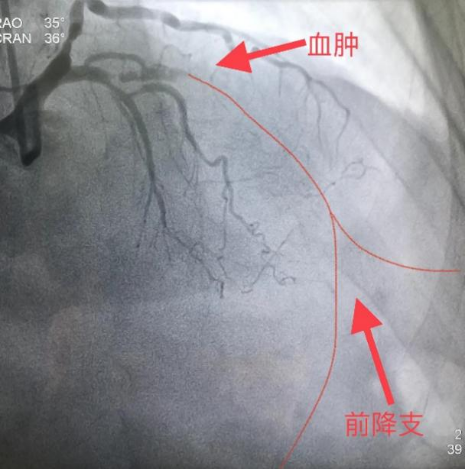

2月中旬,某患者,牛XX,男性,55岁,因冠心病、不稳定型心绞痛入住安徽省阜阳市人民医院,选择性冠状动脉造影(coronary angiography,CAG)示前降支7段和回旋支13段为CTO,右冠脉2段为重度狭窄,病变复杂,病情危重(图1)。当地医院反复尝试,历时约2小时前降支和回旋支均未能开通,遂建议患者3月后再次尝试PCI或选择CABG治疗。患者2月后慕名去武汉亚洲心脏病医院接受介入治疗,但尝试约2小时仍然未能开通前降支CTO(图2),建议患者接受CABG治疗。

图2 武汉亚洲心血管病医院手术资料